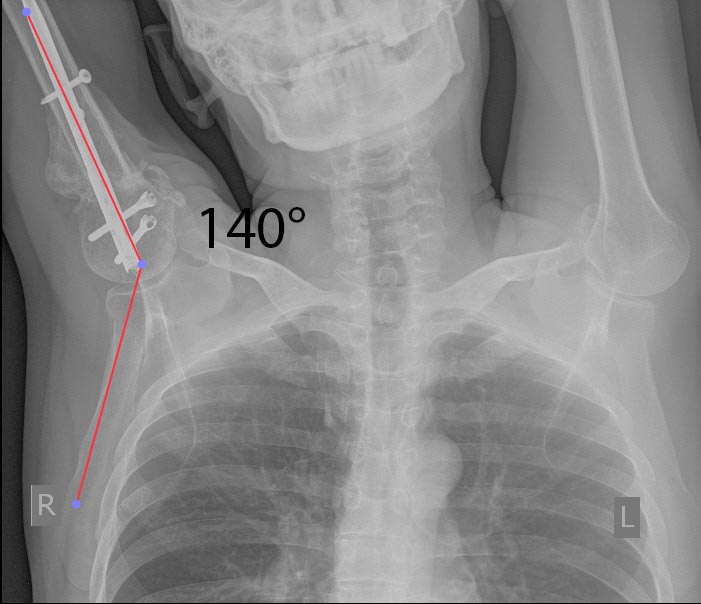

А насчет функции - вот примерчик. До и после коррекции.